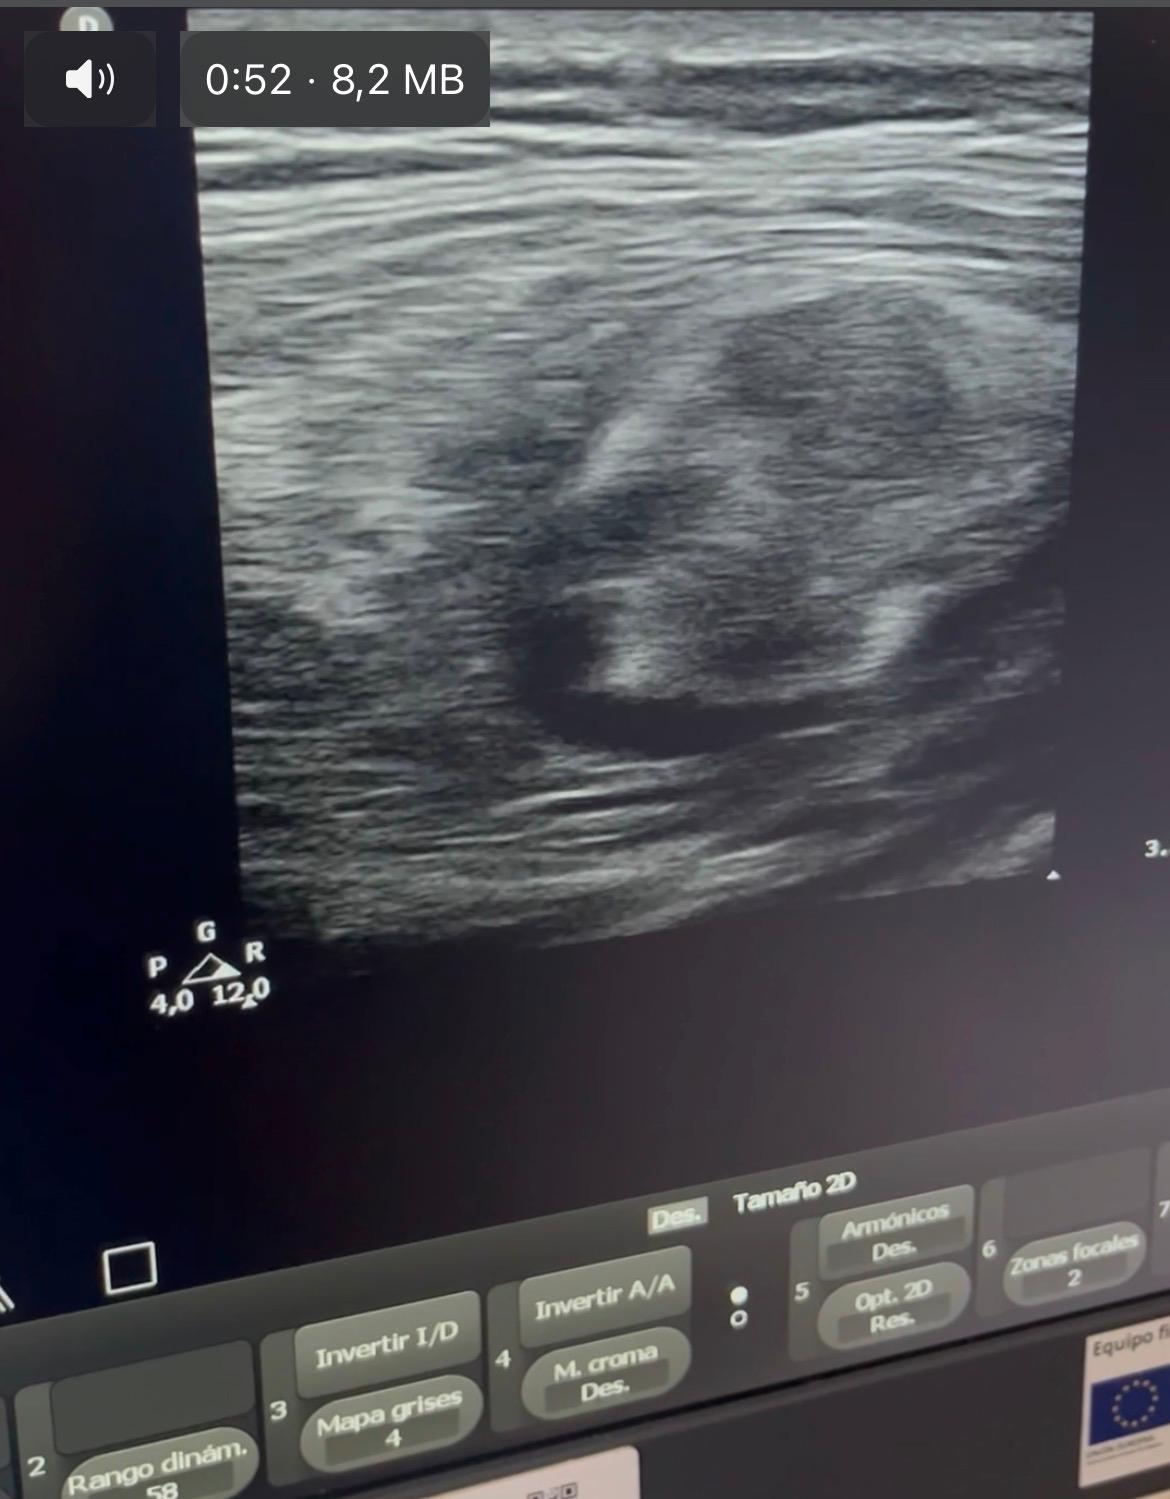

Hallazgos ecográficos

Ecografía clínica con sonda lineal: lesión mal definida, heterogénea, con áreas hiperecogénicas e hipoecoicas, vascularizada, de aproximadamente 5x7cm, sospechosa de malignidad.